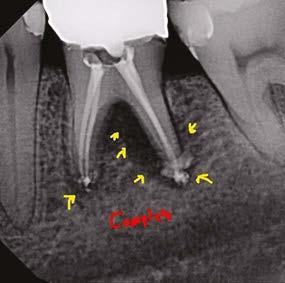

5A-5B: CBCT was taken during initial endodontic exam in 2023. 5A. Coronal CBCT

revealed a 6.1 mm x 3.0 mm hypodensity extending from the apical and distal aspect of No. 11. 5B. Sagittal

slices revealed the presence of bone between tooth No. 11 and implant No. 12

spacing of 3.4 mm between the two was noted (Figure 4). The recommended amount of space between a natural tooth and dental implant should be 1.5 mm-2 mm, proving adequate spacing in this case.15 Coronal views of the CBCT evaluation revealed a 6.1 mm x 3.0 mm hypodensity extending from the apical and distal aspect of tooth No. 11 (Figure 5A). Sagittal slices revealed the presence of healthy bone morphology between the distal border of the hypodensity on tooth No. 11 and implant No. 12, thus the hypodensity did not extend to the implant (Figure 5B). Reference was made to the Treatment Options for the Compromised Tooth: A Decision Guide published by the AAE in 2017 to determine prognosis.16 In evaluating the coronal tooth structure, tooth No. 11 had a well-fitting crown with adequate margins, no need for crown lengthening, and required only routine endodontic treatment placing it in the favorable category. The periodontal condition of tooth No. 11 was also favorable with probing depths equal to or less than 3 mm and a normal periodontium. Lastly, the apical periodontitis was expected to resolve following non-surgical root canal treatment.16 Thus, tooth No. 11 was diagnosed as pulpal necrosis with asymptomatic apical periodontitis with a favorable prognosis. Nonsurgical root canal treatment was planned, and informed consent was obtained.

Figure 4: Sagittal CBCT slice revealed 3.4 mm of space between the apex of tooth No. 11 and the mesial border of implant No. 12